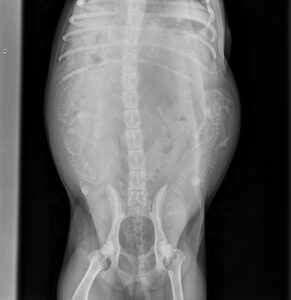

Aster went to the vet today for a pregnancy count x-ray. The vet clearly saw 6 puppies, and said everything looked good. ChatGPT analyzed the two x-rays and counted 7 puppies. So, in a couple of days we shall see. Aster is in the final stretch.